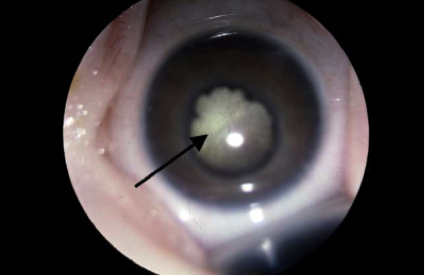

El síndrome de la osteoporosis-seudoglioma es un trastorno autosómico recesivo muy poco frecuente que se caracteriza por una ceguera congénita o que aparece en la infancia y por una osteoporosis juvenil severa con fracturas espontáneas. Otras manifestaciones clínicas adicionales pueden incluir: microftalmia, anomalías del iris, el cristalino o el cuerpo vítreo, cataratas, baja estatura, microcefalia, laxitud de los ligamentos, retraso mental e hipotonía.